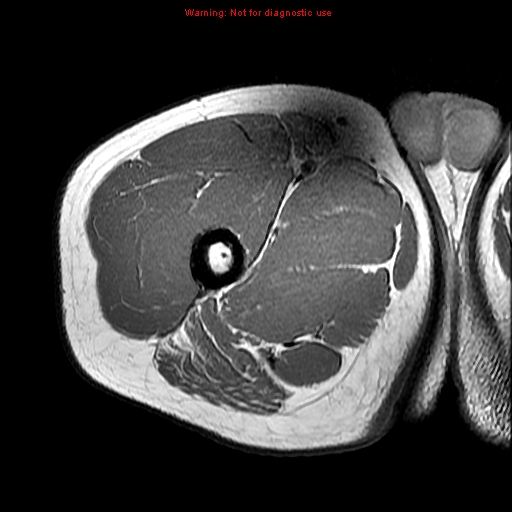

vastus medialis muscle rectus femoris

rectus femoris

sartorius muscle

sartorius muscle popliteal artery

popliteal artery

biceps femoris

vastus intermedius